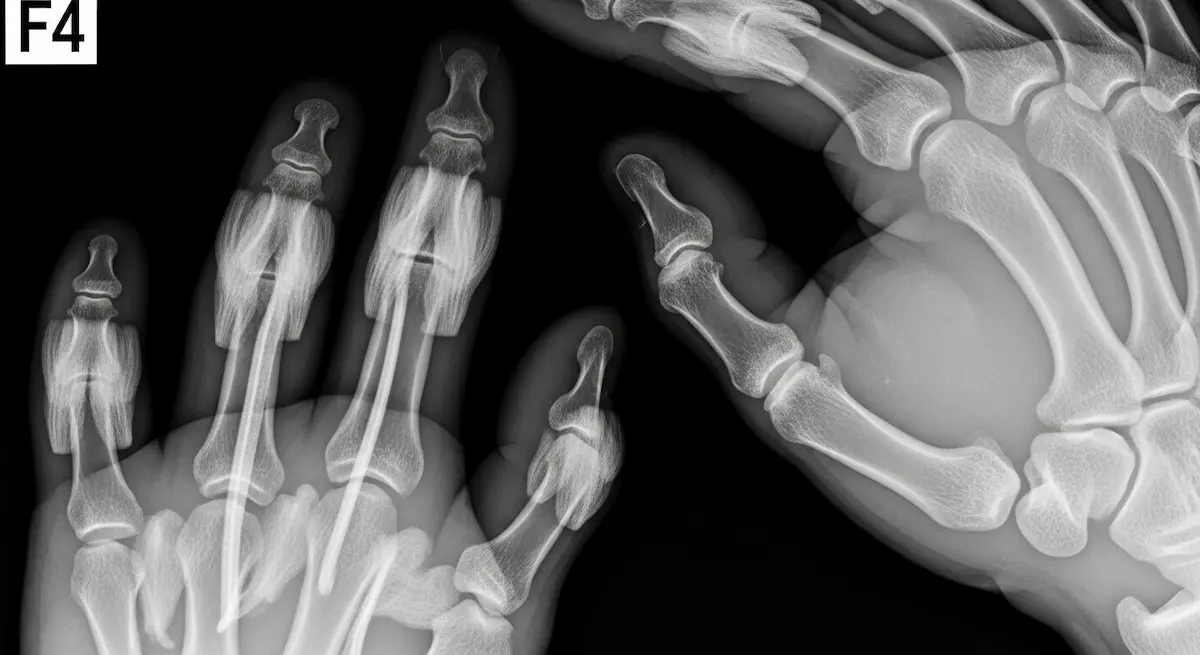

Como cirurgião especialista em cirurgias minimamente invasivas da mão e punho, uma das perguntas mais frequentes que recebo dos meus pacientes é: quanto tempo de recuperação da cirurgia no dedo da mão é necessário para retomar as atividades normais? Essa…